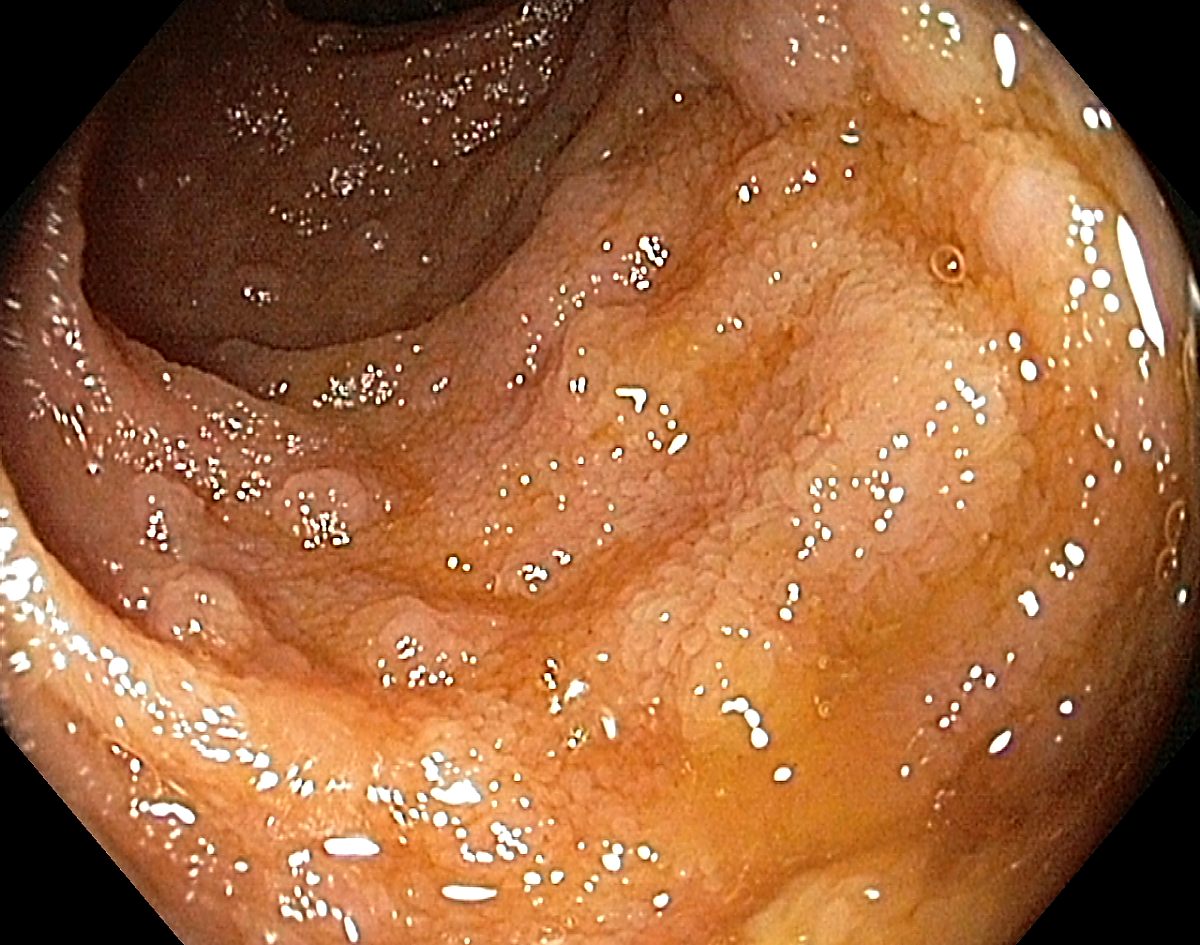

Lymphoid hyperplasia in the terminal ileum - an innocent finding